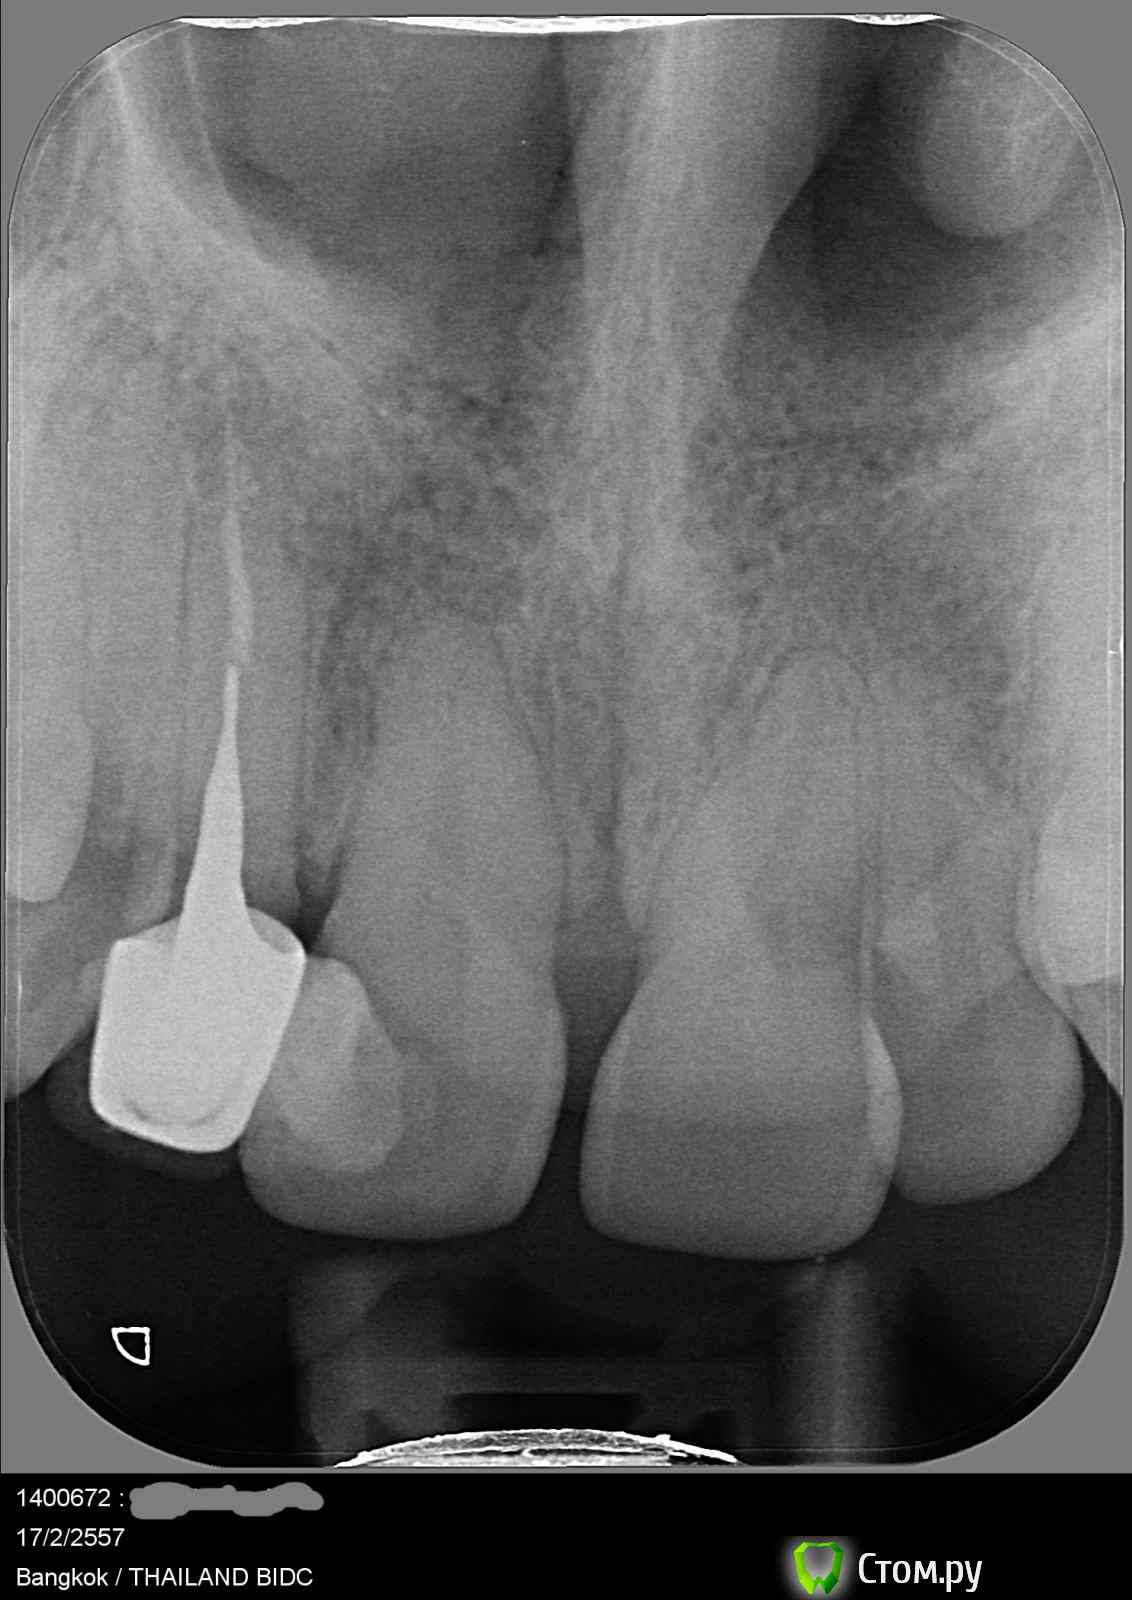

Правый верхний первый резец. Оказалось, что под пломбой полость. Стоматолог сказала, что полость большая и что по рентгену ей непонятно насколько близко она подходит к нерву и станет понятно только после того, как пломбу вытащат и полость почистят. Если полость подходит не близко, то зуб просто заново запломбируют. При этом варианте по ее предварительной оценке это поможет на год примерно и что лучше все-таки сразу поставить коронку. Я так поняла, что это потому что зуб передний, тонкий и при такой большой полости гарантий того, что все будет держаться, мало. Если полость подходит близко к нерву и затронут канал, то по ее словам нужно будет лечение канала и потом ставить коронку.

Сегодняшние результаты (февраль 2014) - то, что мне сказала стоматолог. Между коронкой и корнем зуба есть полость, и есть воспаление на остатке корня (в самой глубокой его части - там где оно и раньше обнаруживалось). Варианты лечения этого зуба, которые она предложила: снять коронку и штифт, проверить насколько сильный этот остаток корня. Если сильный, то пролечить канал, вставить новый штифт и новую коронку. Если остаток слабый, то ставить мост или имплант. По мнению этого врача остаток корня на снимках выглядит так, что даже если он сильный, то коронка простоит лет 5, а дальше уже как повезет.

post-37722-0-14435700-1392636447_thumb.jpg